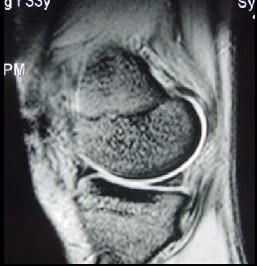

问题 男性,年龄50岁,自诉3年前有轻微的右膝关节外伤史,现感右膝关节不适,请结合所提供的图像,选择最佳选项 ( )

选项 A、左膝半月板囊变 B、左膝左膝关节积液 C、左膝关节骨关节病 D、左膝半月板损伤 E、左膝半月板退变

答案 E